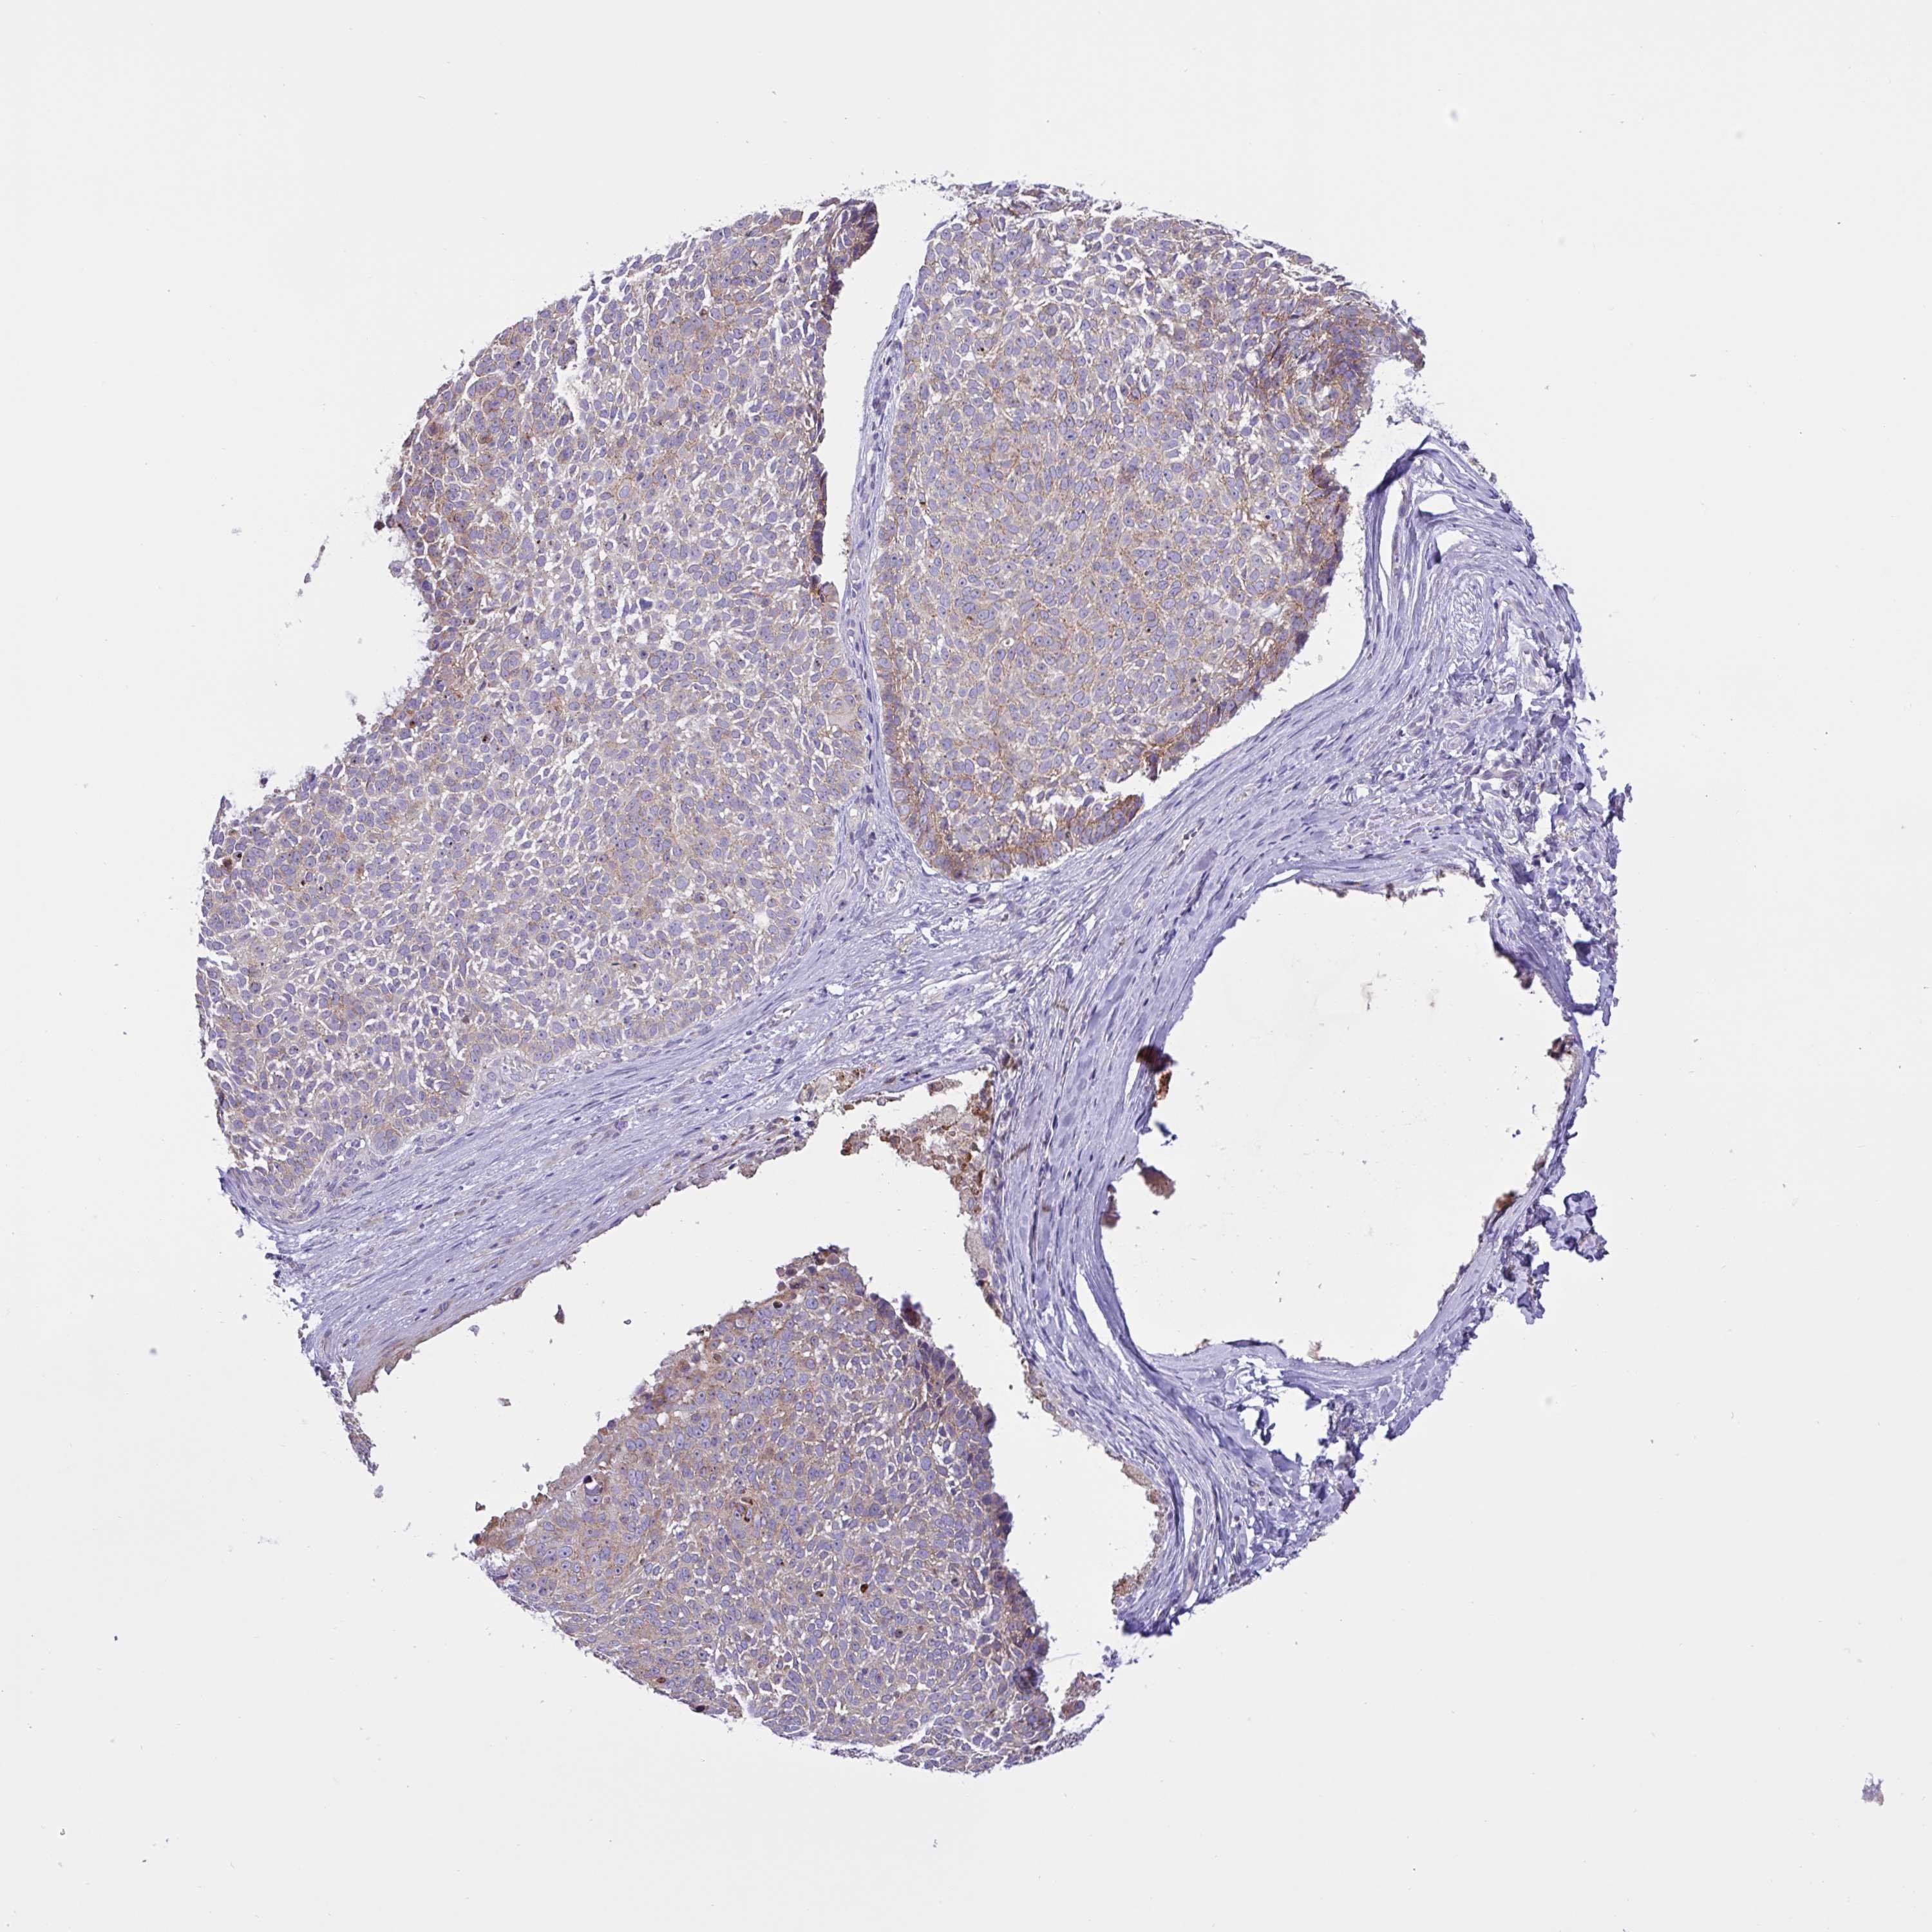

Basal cell and squamous cell cancer

SKIN CANCER - Protein expressioni

A mouse-over function shows sample information and annotation data. Click on an image to view it in a full screen mode. Samples can be filtered based on level of antibody staining by selecting one or several of the following categories: high, medium, low and not detected. The assay and annotation is described here.

Each image is clickable and will lead to virtual microscopy that enables deeper exploration of all samples and also displays staining intensity scores, fraction scores and subcellular localization as well as patient and tissue information for each sample.

Antibody CAB037328

Squamous cell carcinoma, NOS